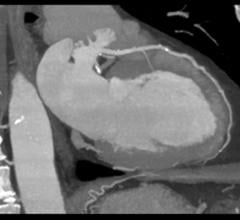

September 25, 2020 — Based on its recent analysis of the global artificial intelligence (AI)-based echocardiography ...

September 25, 2020 — A study out of University Hospitals (UH) found that removing the cost barrier for coronary artery ...